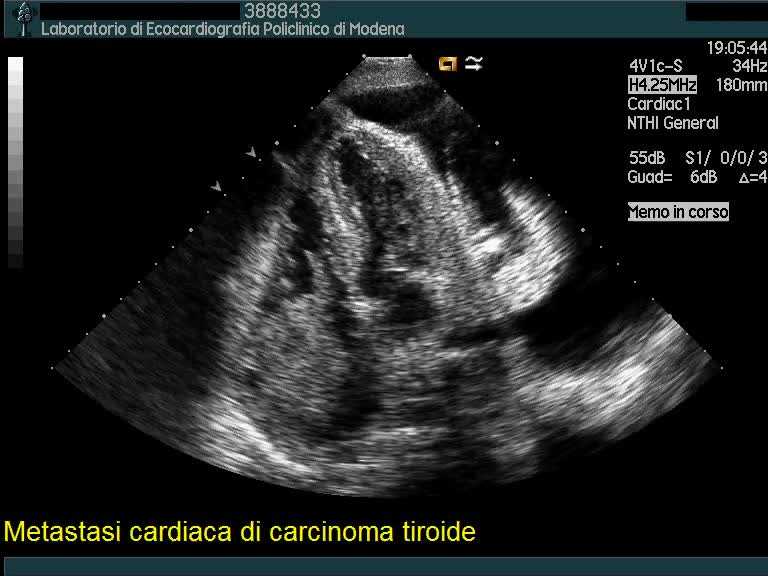

Titolo:

Metastasi cardiaca di carcinoma tiroideo

Autore:

Andrea Barbieri